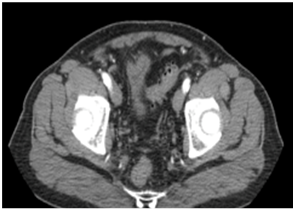

We report a case of a 72 years-old male patient who had history of previous purulent drainage through the belly bottom during the last 18 months. He had undergone to open appendectomy 14 years ago. During these episodes local treatment with topical antibiotics was performed with partial resolution. He came to the clinical office complaining about purulent discharge through the umbilicus again. CT showed a 4 cm fluid collection located in the infraumbilical middle line, communicating with the belly bottom (Figure 1 & 2). The patient accepted to undergo surgery. We performed a laparoscopic approach. Before portal placement and pneumoperitoneum we dissected the infected area inside the umbilicus, sutured with 2-0 Vycril® and left the specimen inside the abdominal cavity. Figure 3 demonstrates our standard ports placement. After this, we placed a 10 mm port, 8 cm above the belly bottom and started the pneumoperitoneum. The camera was placed in this trocar. Another two 5 mm ports were placed lateral to the rectus abdominis, one for a grasper and the other for scissor (Figure 4) Adhesions were perceived during cavity inspection.. We dissected the urachus and. a retained suture material with intense inflammatory reaction was identified (Figure 5). Bladder resection was not needed. The surgical specimen was removed through a 5 mm portal. Fascia was sutured with 0 Vycril®. Estimated blood loss was not quantified. Operative time was 94 min.Patient was discharged 24 h after the procedure and no early or late complications were reported after 60 days of follow-up. Pathology report demonstrated fibrotic connective tissue with chronic inflammation and foreign body granuloma in a 6.0 x 2.0 x 1.8 cm specimen.

Figure 1 & 2 CT sc an demonstrated images suggesting an infected urachusremnant.